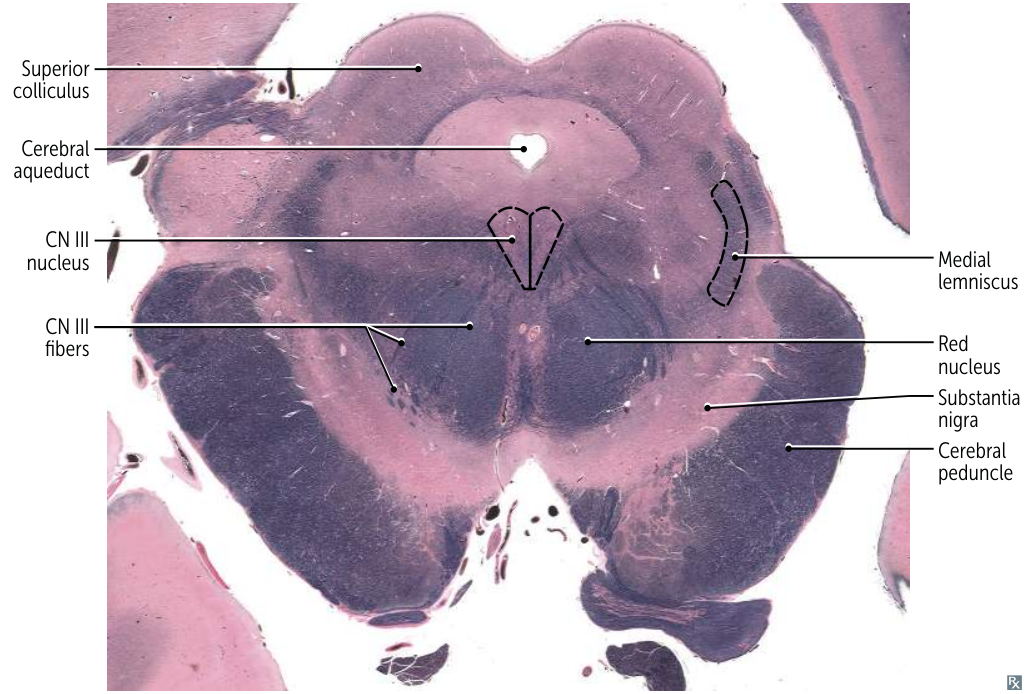

Rostral Midbrain (at Superior Colliculus):

- Most Distinctive Feature: Presence of the large, circular Red Nucleus and the Superior Colliculus. CN III nucleus/fibers are also visible.

- Mnemonic: “Red eyes on Mickey Mouse” (Red Nucleus, CN III ocular motor nucleus, Mickey Mouse shape of cerebral peduncles).

- CN III (Oculomotor) nucleus: Controls most eye movements, pupil constriction, and lens accommodation.

- CN IV (Trochlear) nucleus: Controls the superior oblique muscle of the eye.

- (Also contains the Mesencephalic Nucleus of CN V, which handles proprioception from muscles of mastication).